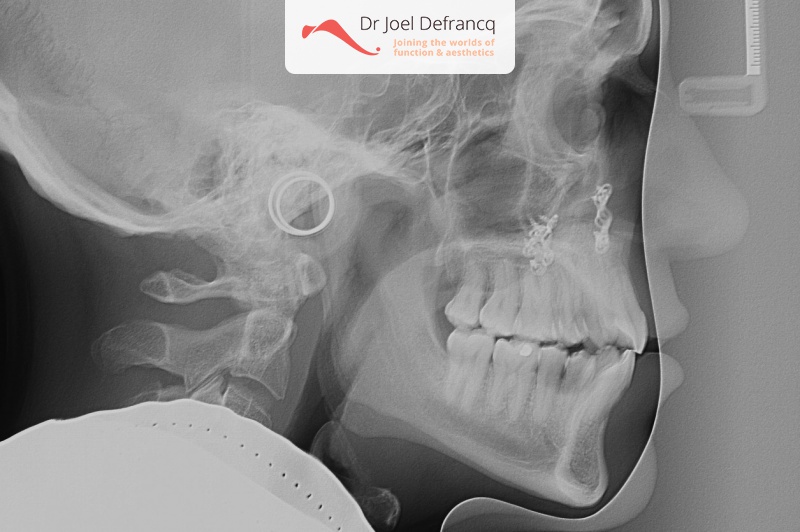

Natan: Kaakchirurgie voor en na. Te nauwe bovenkaak

Kaakchirurgie

- Verlenging bovenkaak (Le Fort I)

- Verbreden bovenkaak (Smile distractor)